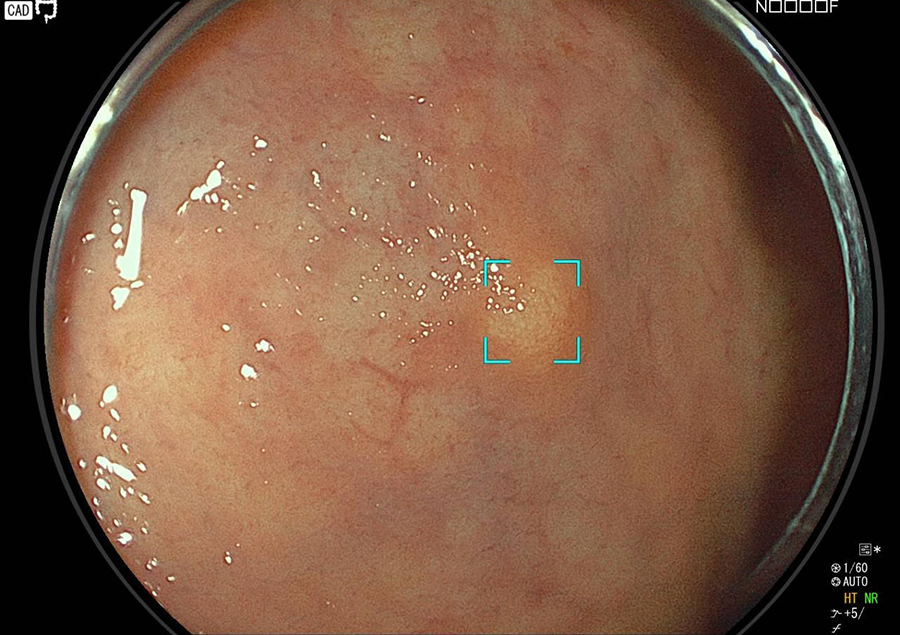

検査の様子

大腸カメラはポリープやがんの発見と診断に、最も精度の高い検査法です。

近年、大腸がんが急速に増加していますが、がんの芽となるポリープ(腺腫)、一部の早期がんは、大腸カメラによる内視鏡治療で完治させることが可能です。

そこで当院では大腸カメラ検査時にポリープや早期がんが発見された場合は、可能な限り積極的にその場で切除しております。